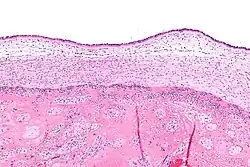

Micrograph showing acute chorioamnionitis, with neutrophils in the chorion. Also seen are fibrin thrombi, which indicate a severe fetal inflammatory response.[1] H&E stain.

Infiltration of the chorionic plate by neutrophils is diagnostic of (mild) chorioamnionitis. More severe chorioamnionitis involves subamniotic tissue and may have fetal membrane necrosis and/or abscess formation.[1]